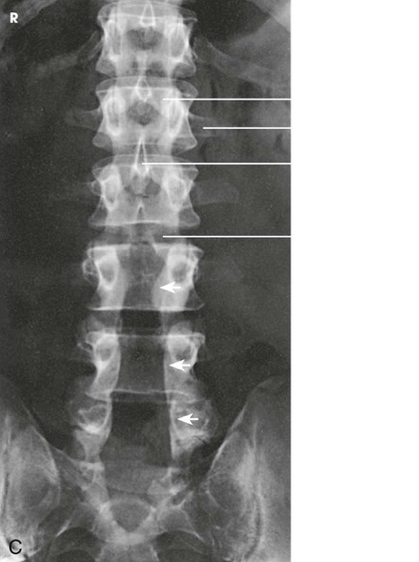

Question

Label the image

7b715ad3-6c1f-467d-8dbc-9bbfbe4881fb (image/png)

Answer

L4

S1

spinous process

intervertebral disk space

iliac crest